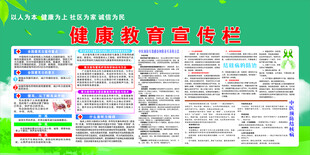

中医健康教育知识宣传 共享分:100

中医健康教育知识宣传 共享分:100 -

中医健康教育宣传栏 共享分:40

中医健康教育宣传栏 共享分:40 -